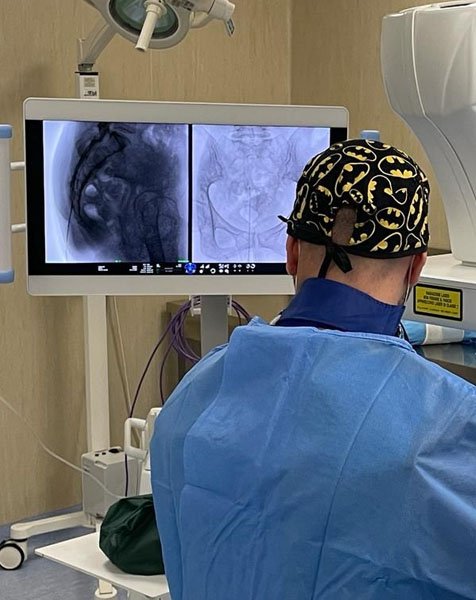

L’epidurolisi è una tecnica mininvasiva che prevede, sotto guida fluoroscopica ed in anestesia locale o blanda sedazione, l’introduzione di un catetere/elettrodo che attraverso una lisi meccanica e farmacologica, permette lo sbrigliamento delle radici nervose riducendo così la sintomatologia dolorosa. È possibile, inoltre, attraverso la punta di questo particolare elettrodo, eseguire la radiofrequenza pulsata gangliare a più livelli.

CASE STUDY EPIDUROLISI